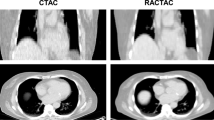

All scans were analyzed using FusionQuant (Cedars-Sinai Medical Center, CA, USA). Anatomically exact co-registration of PET and contrast CT images in the axial, sagittal, and coronal planes using the diastolic gate (50-75% of RR interval) was performed (Figure 2) based upon matching PET tracer uptake in the blood pool of the cardiac chambers and the wall of the ascending aorta with these same structures on the contrast CT angiogram. Correction of image co-registration was done by clicking and dragging the mouse cursor in 3 planes in order to refine alignment in an anatomically exact fashion. ROI definitions were chosen to have similar areas and volumes compared with the most diseased segments approach in OsiriX as follows.5 A 3-dimensional polyhedron with parallel congruent bases and 6-mm height was drawn in the aortic valve plane and adjusted in the z-axis to obtain the highest aortic valve SUVmean value. The SUVmax value in that position was defined as the highest PET activity inside the polyhedron. The average blood pool uptake was measured in a cylinder with 8-mm radius and 9-mm height drawn in the center of the right atrium in an en face view of the aortic valve. Figure 1 shows a comparison of both user interfaces. Instead of utilizing hybrid PET-CT images obtained during the same imaging session, fusion of PET and CT images acquired at different time points would follow the same protocol without additional processing time.

Aortic valve 18F-fluoride analysis with FusionQuant in a patient with aortic stenosis. Region of interest drawn around anatomically exact borders of aortic valve in the valve plane (axial, coronal, and sagittal planes). Panels A, B, and C show misaligned PET and CT images. Through dragging with the mouse, panels (D, E, and F) were achieved. Panels G, H, and I show reduction in PET image noise and improvement in image quality with motion correction